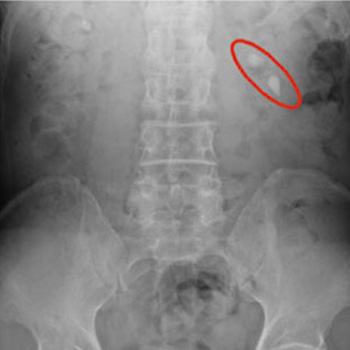

一般撮影

フラットパネルシステムが導入され、画質が向上し、被ばく線量の低減(従来の約40%カット)も図ることができました!